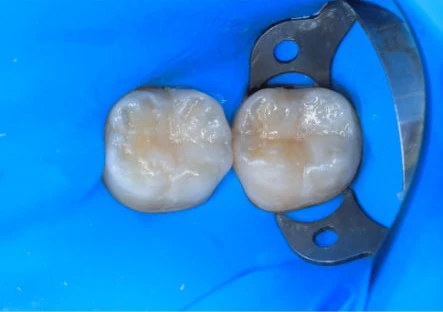

Этапы установки

На этапе подготовки к протезированию рекомендованы диагностика, лечение кариеса и заболеваний десен, а также профессиональная чистка, которые не включены в стоимость коронок Е-мах. Наши пациенты проходят обследование на современном компьютерном оборудовании, что позволяет выявить любые осложнения и противопоказания.

В большинстве случаев все этапы протезирования, включая диагностику, лечение кариозных зубов, изготовление и установку коронок Е-мах, занимают в общей сложности не более 2 недель.

Основные этапы установки Е-max: